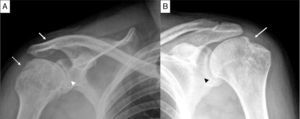

Proyección AP de hombro. A) En el hombro derecho se aprecian erosiones en la tuberosidad mayor (flecha punteada), disminución del espacio glenohumeral (cabeza de flecha) y la anquilosis de la articulación acromioclavicular (flecha). B) En el hombro izquierdo se aprecia disminución del espacio glenohumeral (cabeza de flecha) y el signo del hachazo (flecha).

Varón de 36 años, con inicio de dolor lumbar inflamatorio a los 16 años, limitación de la movilidad lumbar y cervical, artritis de caderas, tobillos y hombros, y HLA-B27 positivo. A los 23 años requirió prótesis bilateral de cadera. Consultó por discapacidad de los movimientos de los hombros, de predominio derecho de un año de evolución. Al examen físico se demostró limitación de los arcos de movilidad para la flexión, extensión y abducción. Sus radiografías mostraron en la pelvis: sacroileítis grado II bilateral; en la columna lumbar: encuadramiento de cuerpos vertebrales y anquilosis vertebral de T11 a L2. En el hombro derecho: cambios degenerativos, erosiones y anquilosis de la articulación acromio-clavicular (fig. 1A); en el izquierdo, disminución del espacio articular glenohumeral, erosión en la tuberosidad mayor del húmero y cambios degenerativos (fig. 1B).